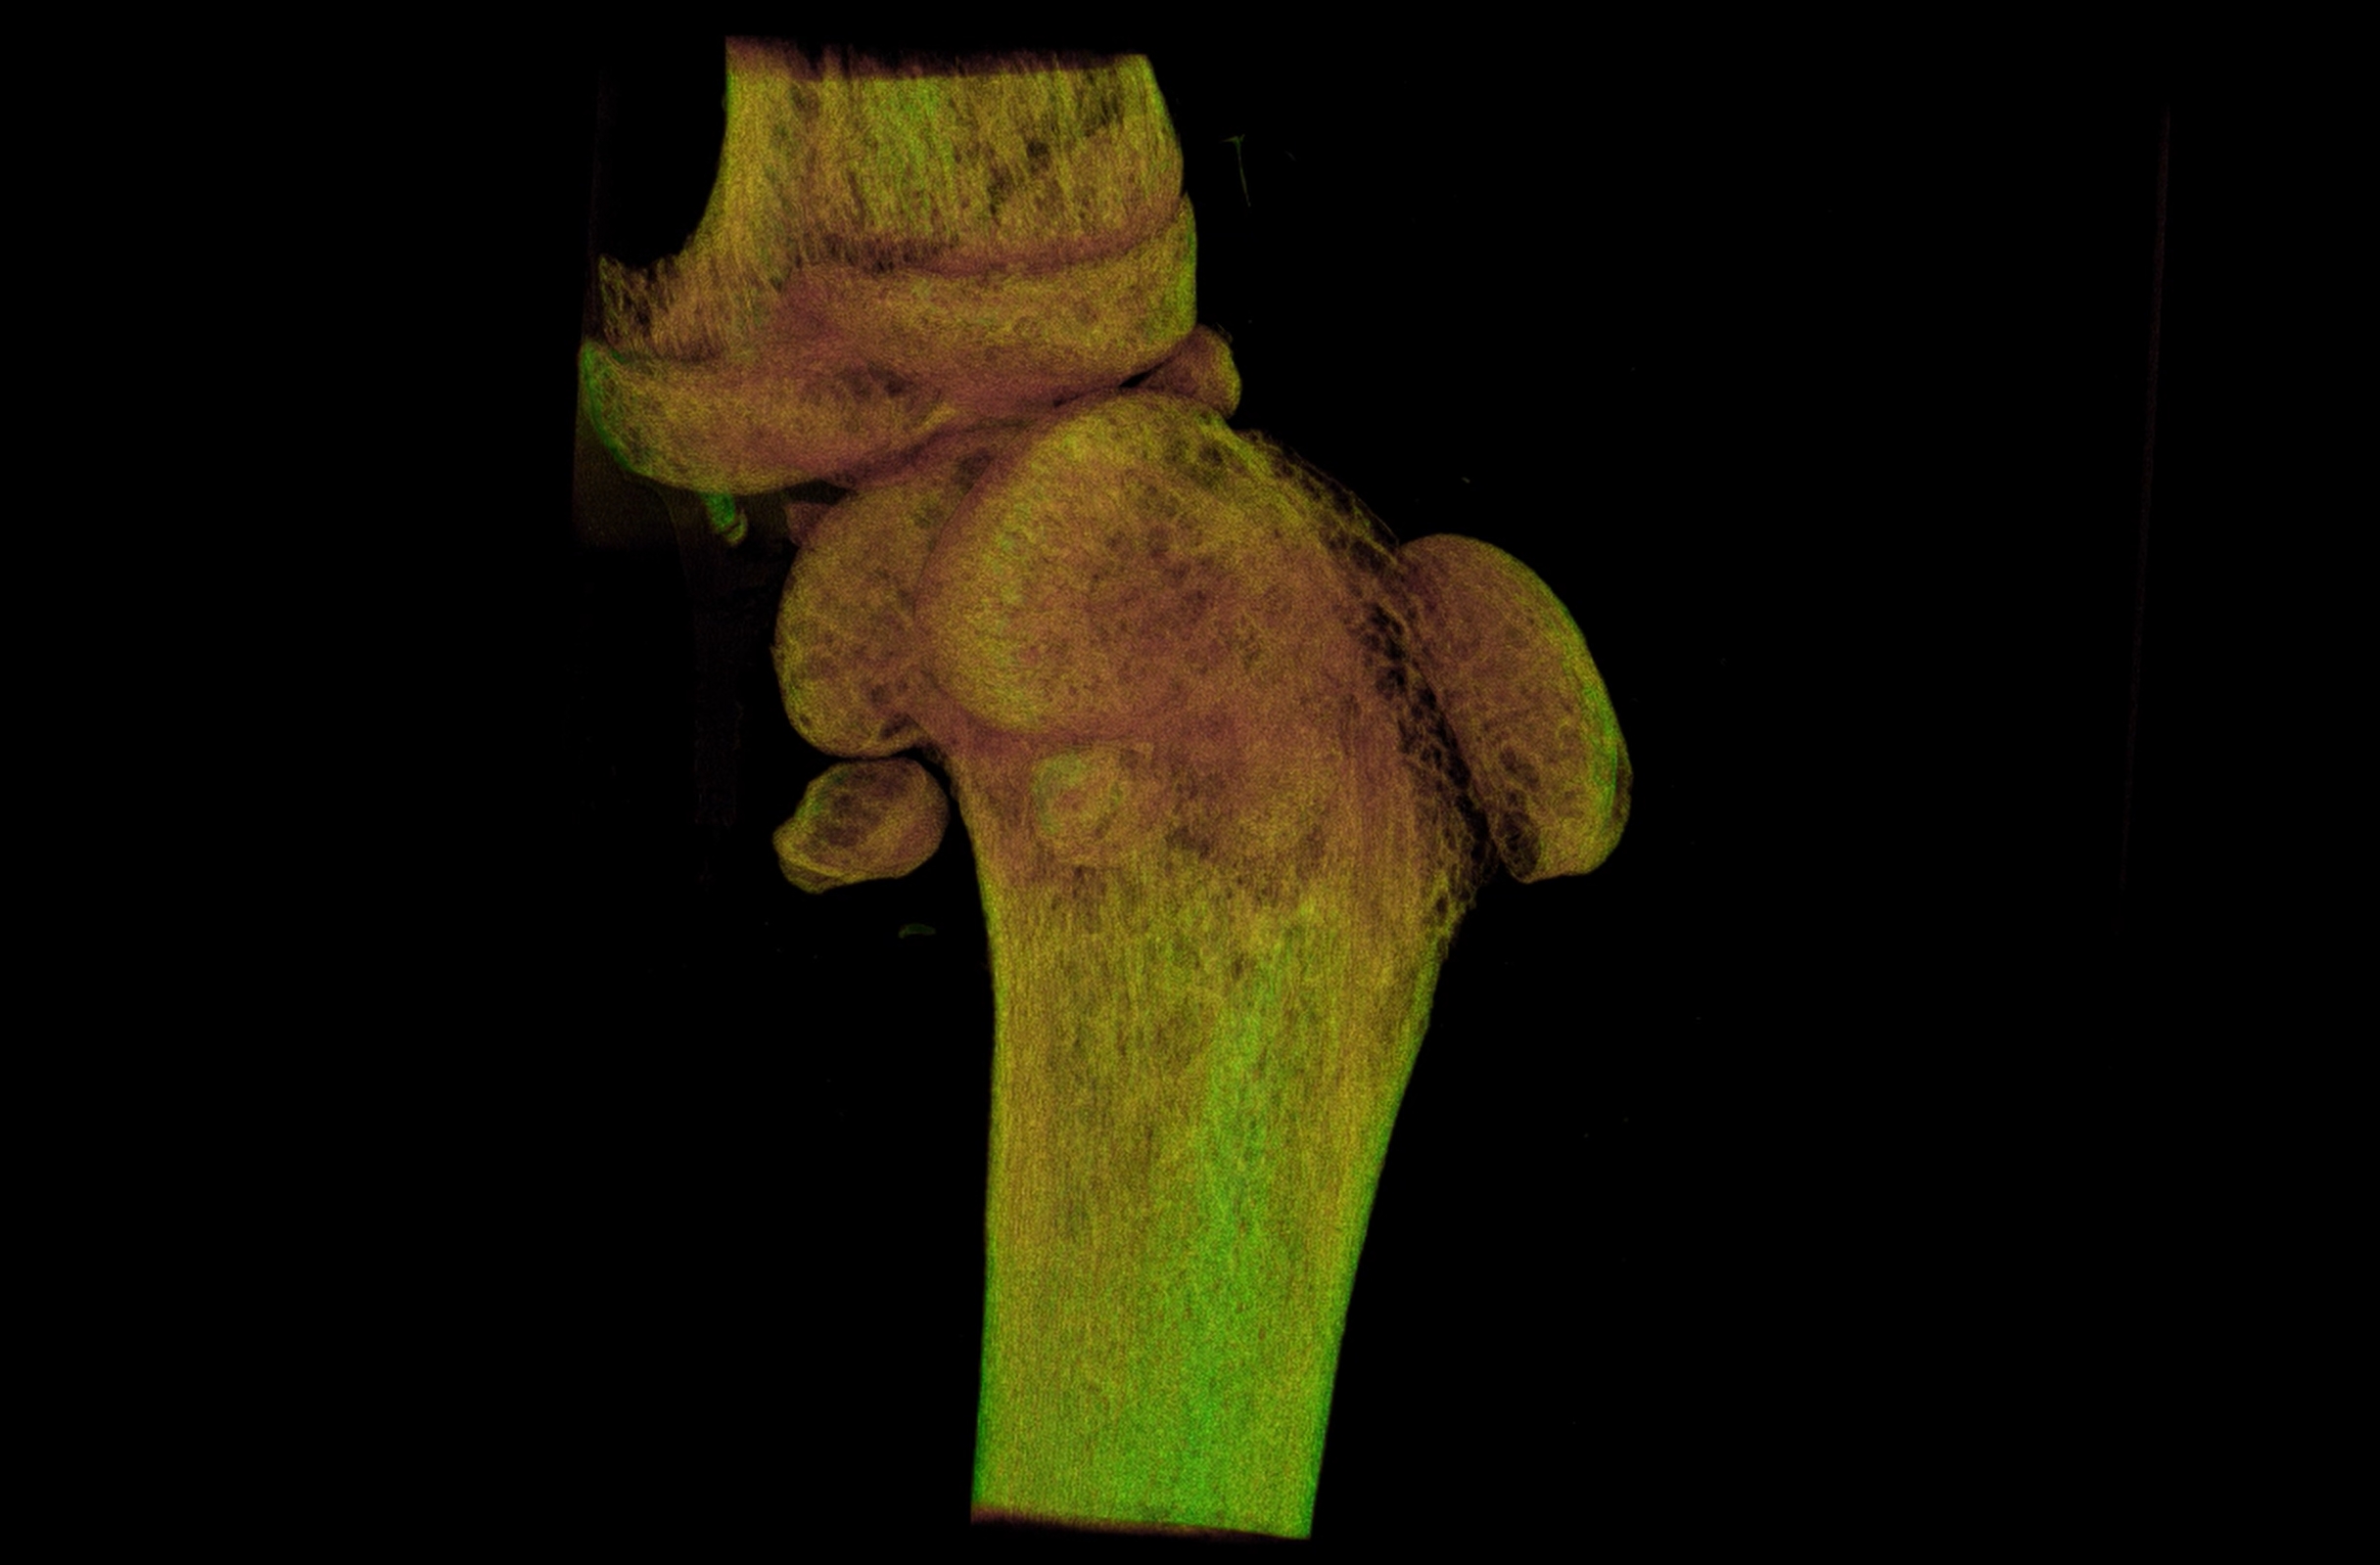

离体小鼠股骨3D重建及彩色渲染

股骨是骨代谢疾病、创伤修复及肿瘤研究的天然模型。例如,在骨质疏松研究中,通过股骨组织工程模型可模拟骨量丢失、微结构破坏过程,揭示骨代谢失衡机制;对于股骨头坏死研究,通过建立缺血模型可动态观察血管再生、骨细胞凋亡过程,为早期诊断标志物筛选提供依据。用动物模型正确理解股骨的解剖和生物力学特征,有助于对其损伤进行合理的治疗。

IMAGING 100是锐视科技自主研发的超高分辨率、离活一体的Micro-CT成像系统。IMAGING 100采用微焦点X射线管和高分辨平板探测器,通过锥形束CT扫描和三维图像重建技术,实现离活一体快速扫描成像。